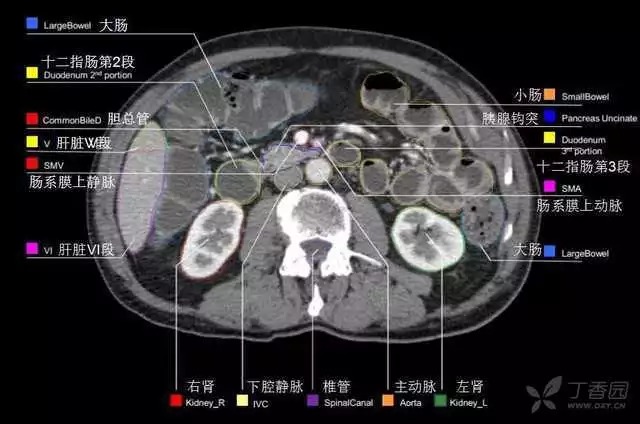

腹部肝脏高清CT断层的图谱

全腹部高清CT图谱,淋巴结彩色图谱,血管解剖图谱大汇总!

超声肝脏分叶及分段

肝脏分段和基本解剖学标志